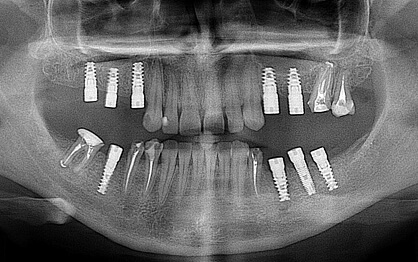

У стоматології процес зазвичай ділиться на два ключові етапи: підготовка і встановлення імплантатів. Вартість протезування зубів на імплантатах можна уточнити у лікаря після огляду та оцінки стану порожнини рота. Для точного розуміння процедури слід розглянути весь процес у деталях, розбивши його на шість кроків:

На цьому етапі лікар проводить обстеження, включно з рентгеном і КТ, щоб оцінити стан щелепної кістки. За необхідності може знадобитися лікування карієсу, усунення запалень або кісткова пластика.

2. Хірургічне вживлення імплантату

Це найтриваліший етап, під час якого нижня частина зуба (імплантат) встановлюється в кісткову тканину. Після операції починається процес остеоінтеграції – приживлення імплантату до кістки.